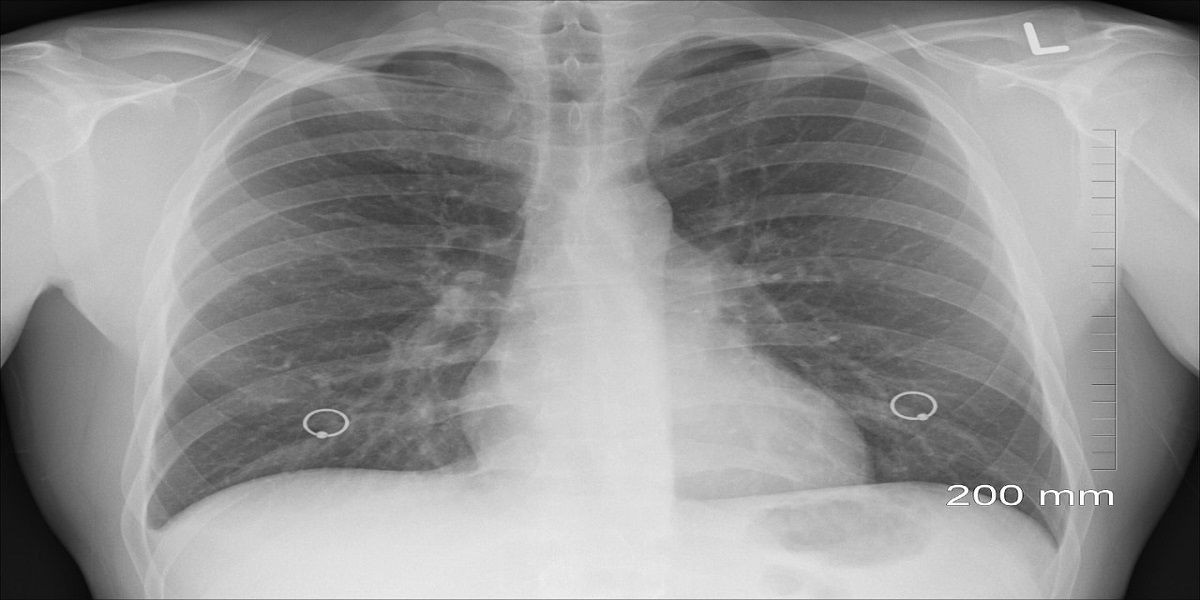

"El esputo (secreción que se produce en los pulmones) de la mujer se examinó para detectar tuberculosis y resultó negativo. Sin embargo, cuando le escanearon el pecho, encontraron una lesión en el lóbulo superior derecho de sus pulmones. Tras una investigación adicional, parecía ser 'una estructura en forma de bolsa invertida' sentada 'en el bronquio'", indica el estudio publicado.

En un primer momento, pensaron que era tuberculosis, una bacteria que casi siempre afecta a los pulmones, pero cuando retiraron esta "bolsa", que estaba casi descompuesta, se dieron cuenta de que se trataba de otra cosa: un preservativo.